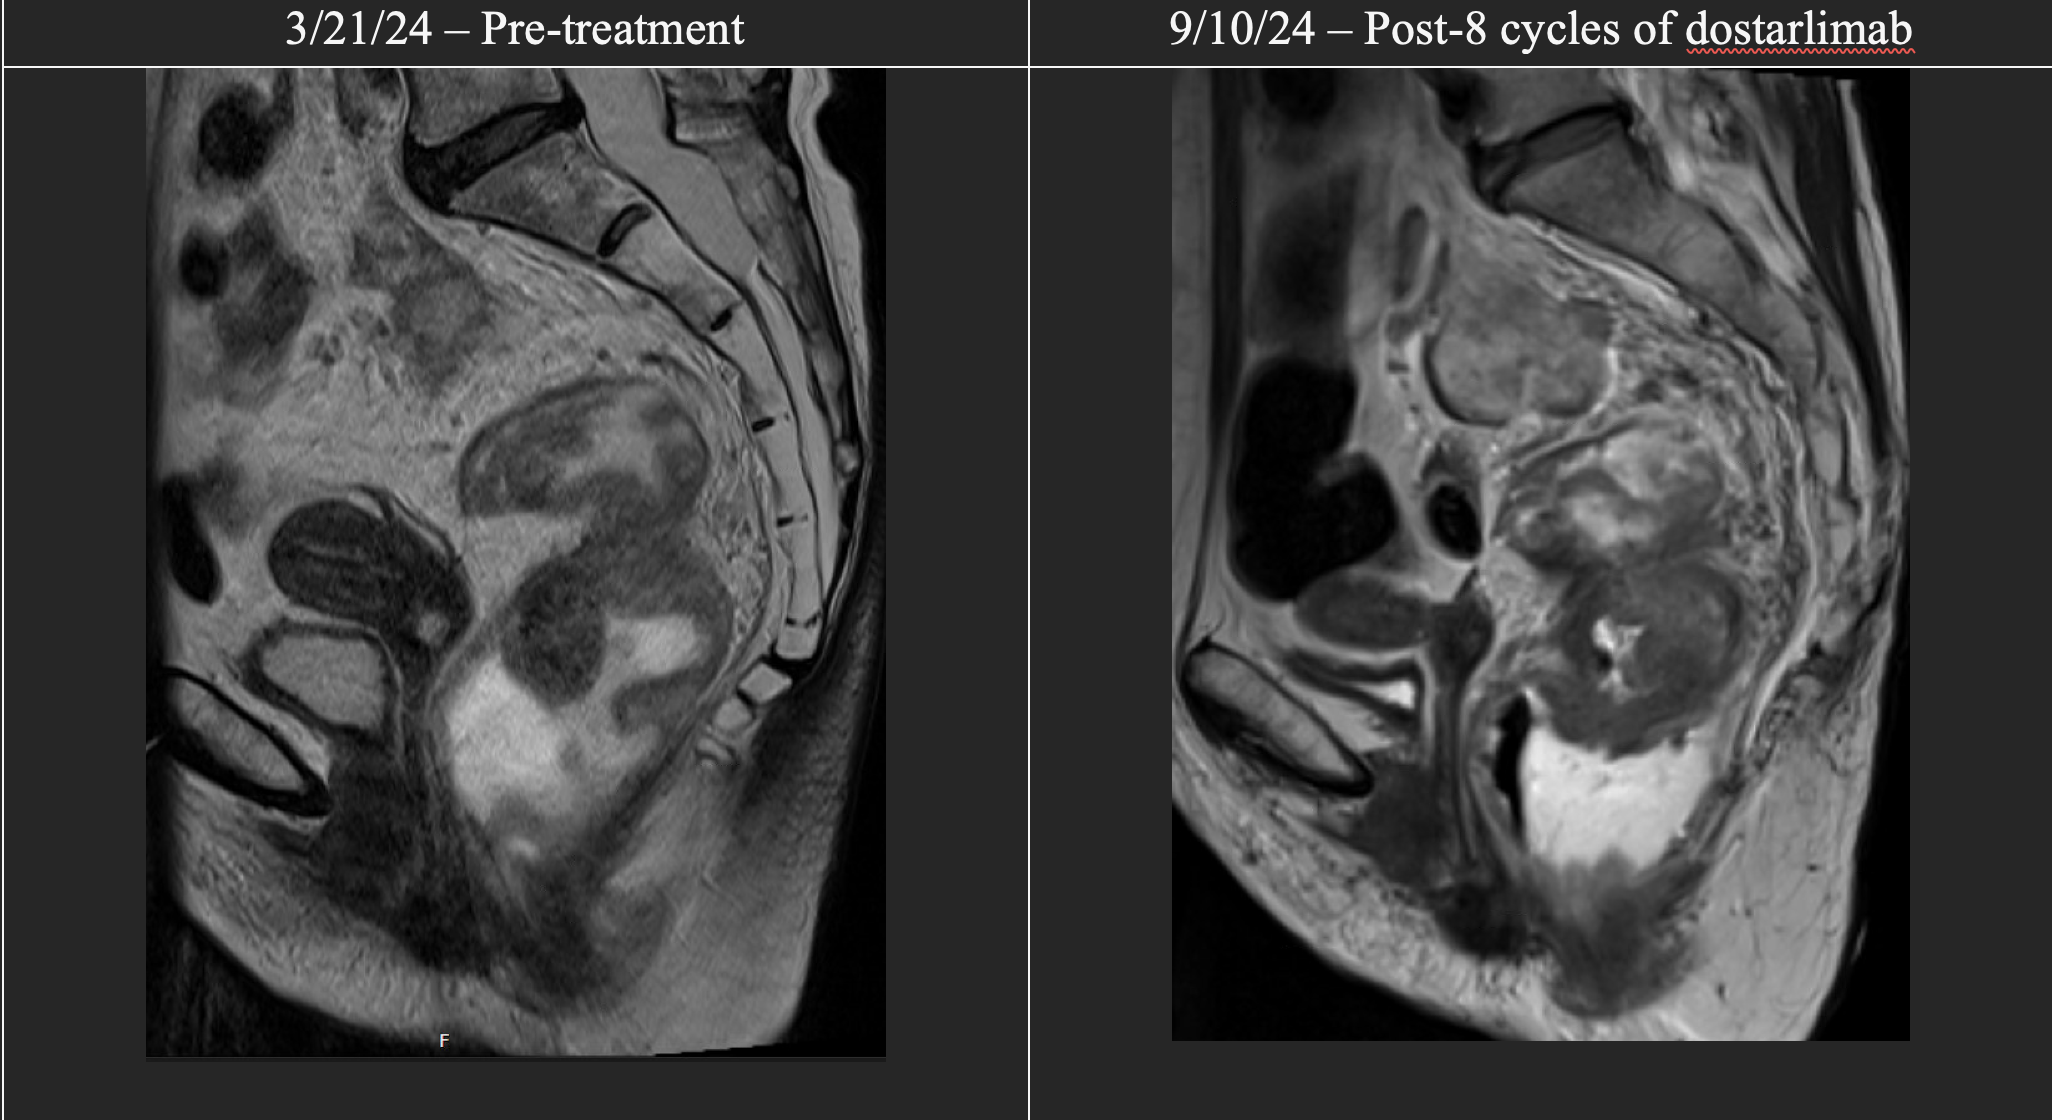

Magnetic resonance imaging-T2 scans of patient in case #2 before treatment initiation and after 8 cycles of dostarlimab. Interval imaging demonstrated essentially unchanged appearance of the primary rectal tumor.